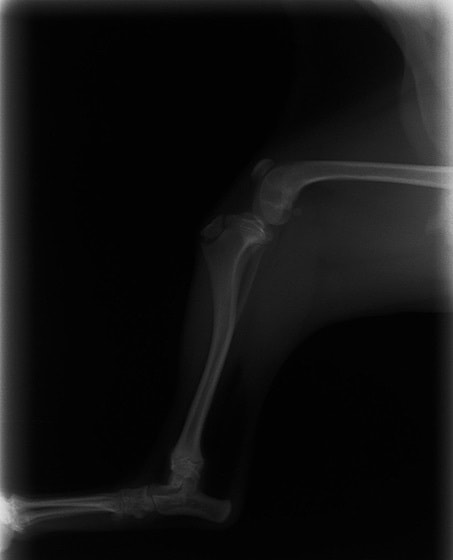

症例3:キルシュナーワイヤーのピンニングによる整復

ペルシャ猫 11ヶ月齢 雄

他院にて左大腿骨遠位の成長板骨折(salter-harrisⅠ型)が認められており、治療相談を目的として来院。当院にて、キルシュナーワイヤーを用いたピンニングにより骨折部位の整復を行いました。術後の経過は良好で、現在も経過観察中です。

術前レントゲン

術後レントゲン

機器

Arthrex社のターゲティングデバイスを用いてピンニングの位置を調整することで、確実な固定を行っています。当院ではこの手術器具以外にも、人の手術にも使用される様々な器具を導入し、手術精度を高め、また医療メーカーと新しい器具の開発、試作にも取り組んでおります。